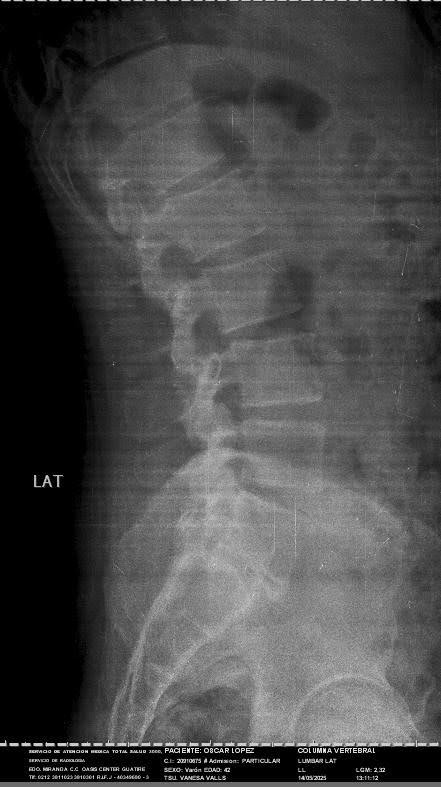

Hello, my name is Oscar. I am 43 years old. I am an orchestral trumpet player, for more than 15 years I was part of the Simon Bolivar Symphony Orchestra, representing Venezuela in thousands of concerts around the world. Today I need your help, due to the economic situation my country is going through, I cannot afford the materials for the arthrodesis I need for my spine surgery. I have been diagnosed with a lumbar disc herniation at the L4-L5 level, accompanied by grade I spondylolisthesis at the L5-S1 level. This has caused severe compression of the lumbar nerve roots, causing constant pain, loss of mobility, and paresthesia. My condition has been evaluated by the medical team, who has indicated the need for imminent spinal surgery.

For several months, I have been suffering from severe lower back pain, which has progressively intensified, radiating to my left lower limb and accompanied by neurological symptoms such as tingling, loss of sensation, and difficulty moving normally.

Furthermore, for a year now, I have been experiencing unexplained urinary symptoms: difficulty initiating urination, a sensation of incomplete emptying, pain and burning, and taking a long time to empty my bladder. After several urological studies, everything points to these symptoms being related to the nerve compression caused by my herniated disc, which increases the urgency of surgery to avoid irreversible damage.